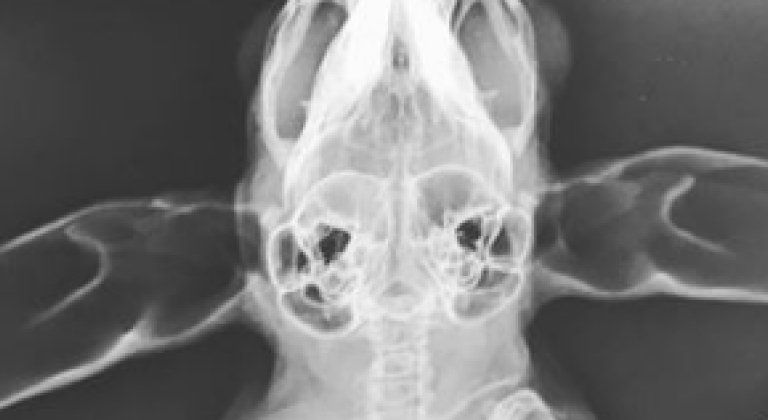

Radiologia

Per tutte queste specie, si tratti di piccoli mammiferi, rettili o volatili, c’è la possibilità di accedere a tutti i servizi veterinari della Clinica: esami del sangue svolti presso il nostro laboratorio interno, diagnostica per immagini e chirurgia.